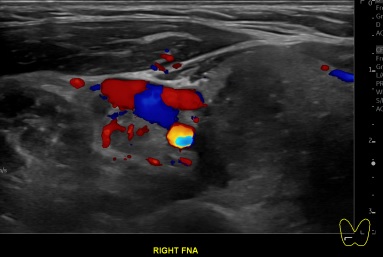

상기환자 외부검사이상소견 세침흡인검사위해 내원하신 20대후반 여성분으로

의심스러운 갑상선 우엽 결절 세포검사 진행후 갑상선암으로 진단되었습니다